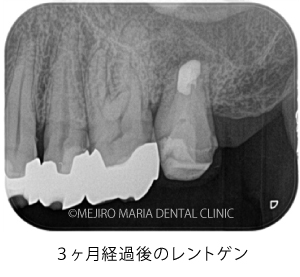

歯根端切除術(意図的再植術)から3週間後の経過観察で、瘻孔の消失が確認できました。また、術後3ヶ月経つと、根尖部付近に確認できていた根尖性歯周炎も小さくなりました。患者様も「噛んだときにも、違和感や痛みなどはない」ということで、予後は良好だと判断しました。今後は最終補綴処置を行う予定です。

今回の症例の患者様は、病変が大きいことから、かかりつけ医に抜歯を宣告されて、当院へ相談に来られました。当院の治療により、瘻孔(フィステル)は消失し、歯根端切除術(意図的再植術)3ヶ月後の経過観察では、明らかな病変の縮小が確認されました。